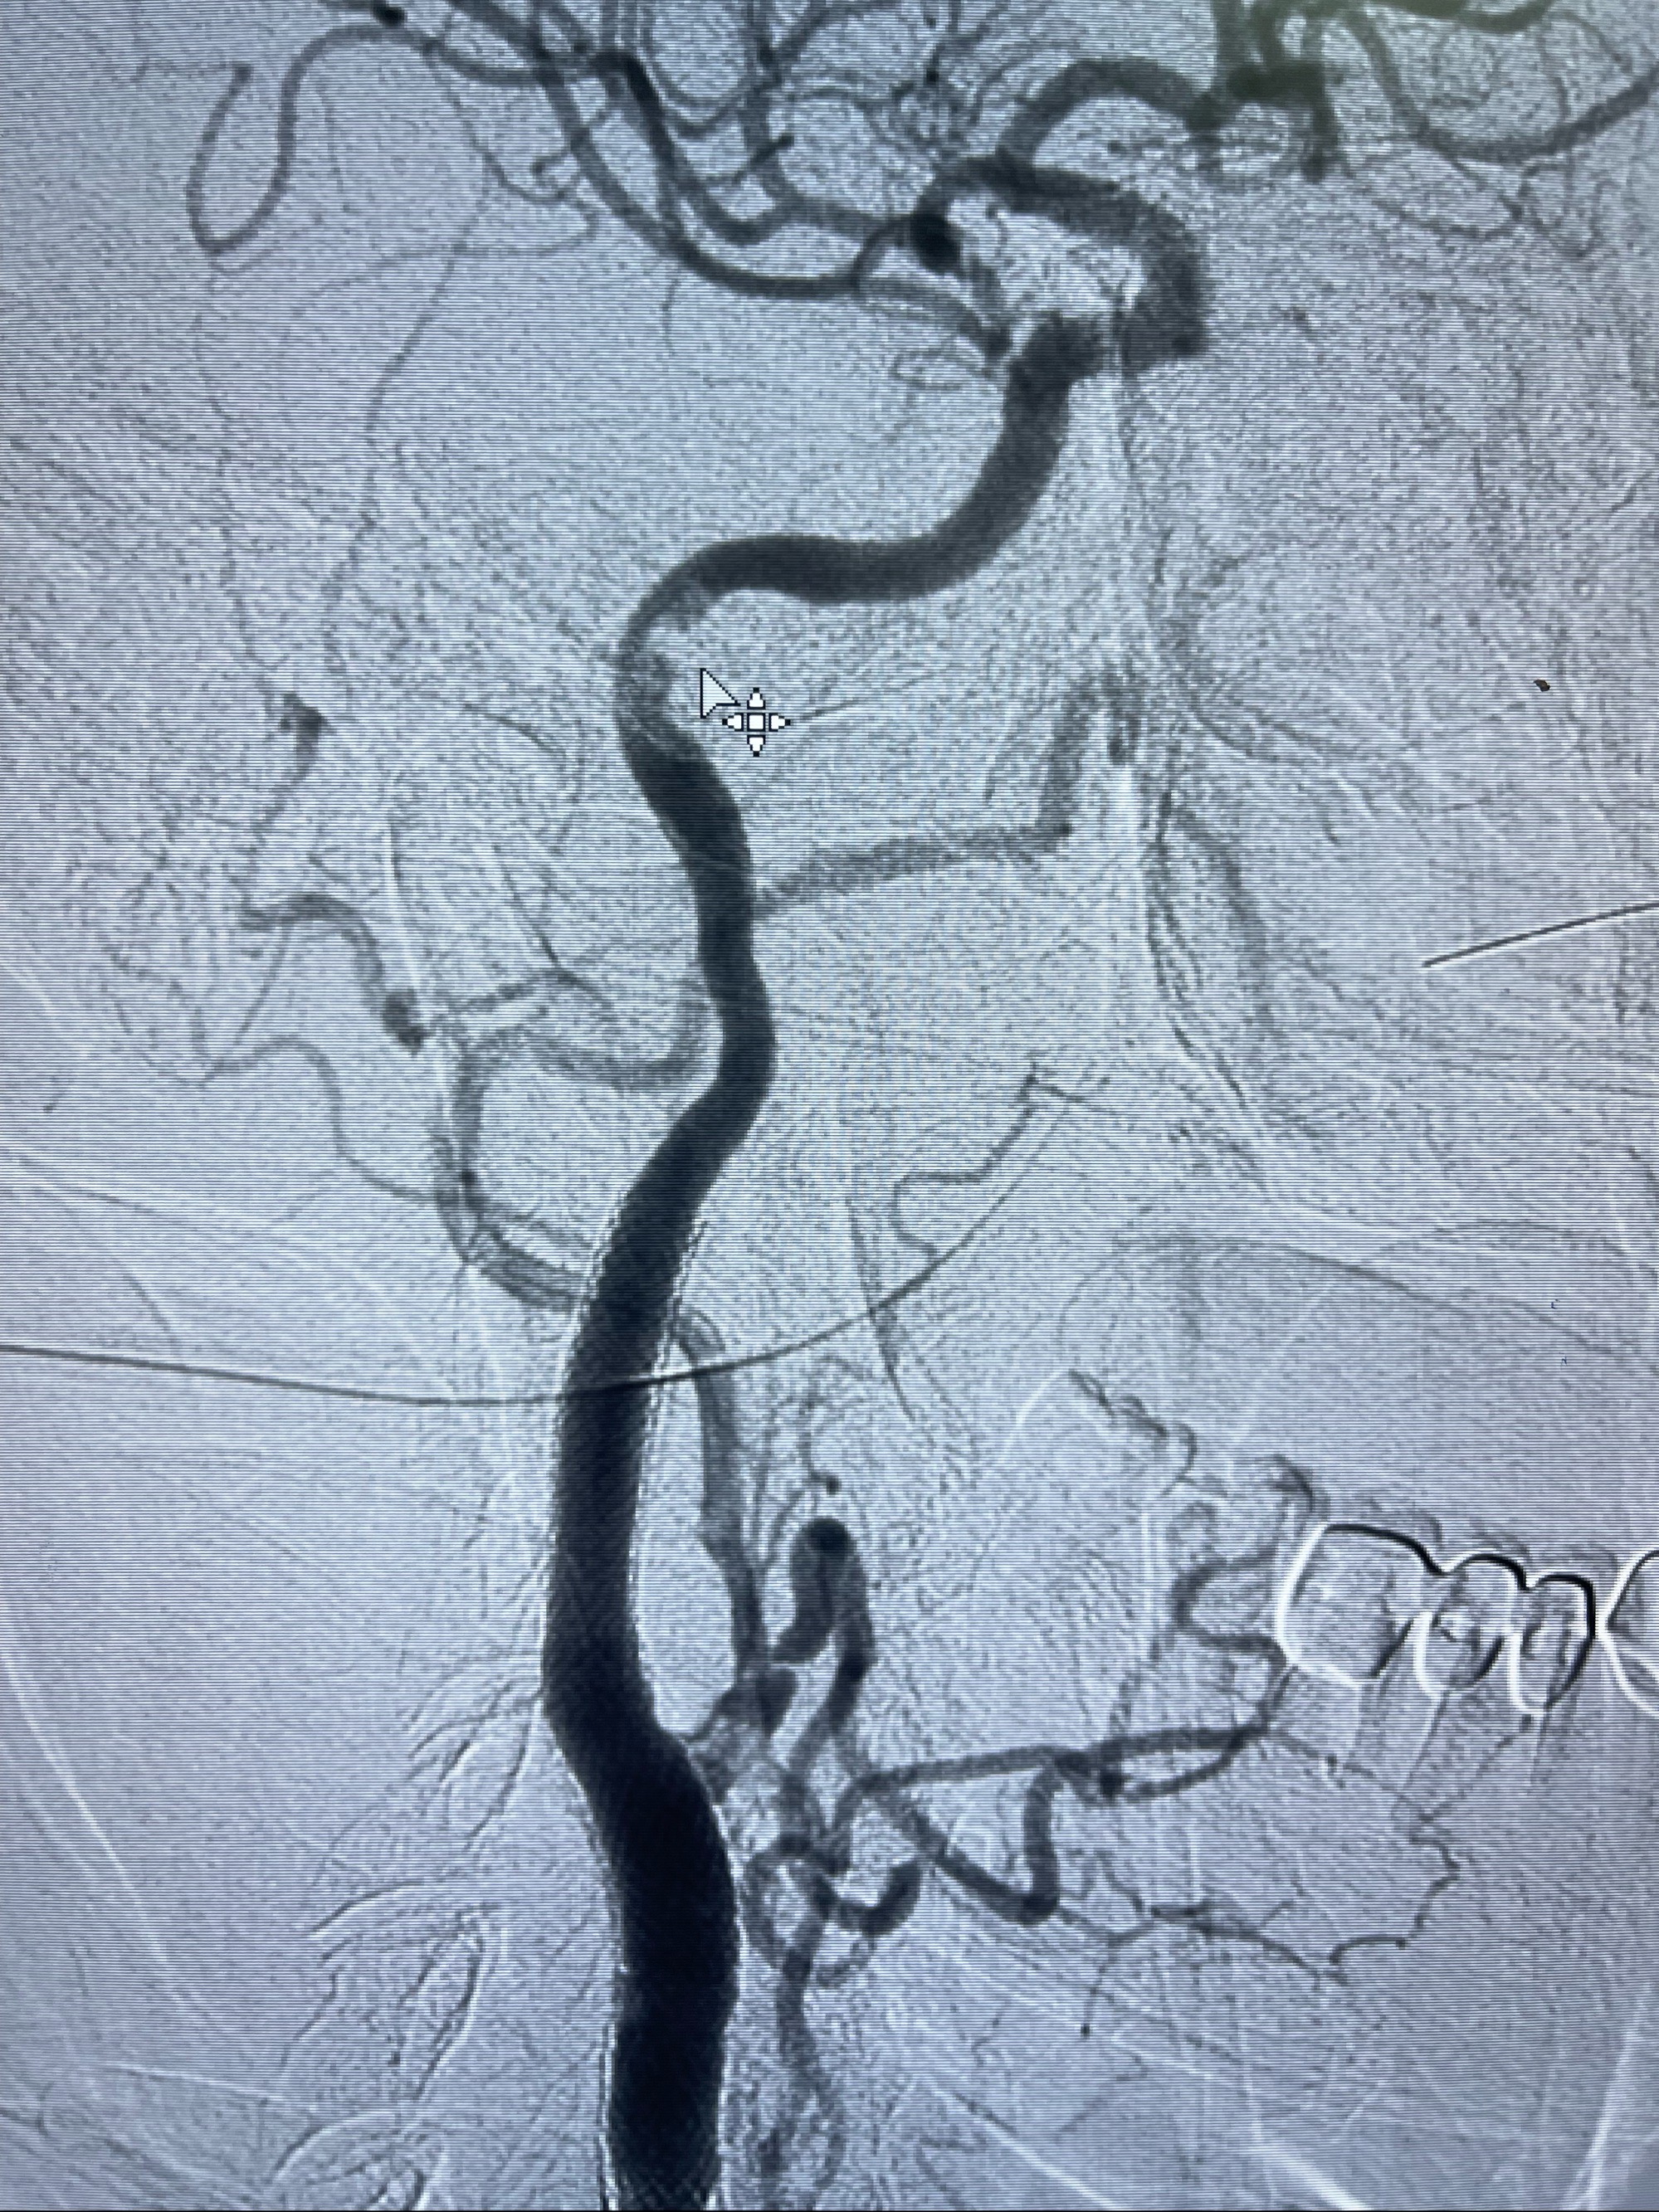

经导引导管造影显示支架远端颈内动脉不规则狭窄伴局部充盈缺损,同时行全身肝素化5ml

泄除球囊造影显示局部管腔扩张佳

即刻造影显示狭窄扩张佳

即刻造影显示支架贴壁佳